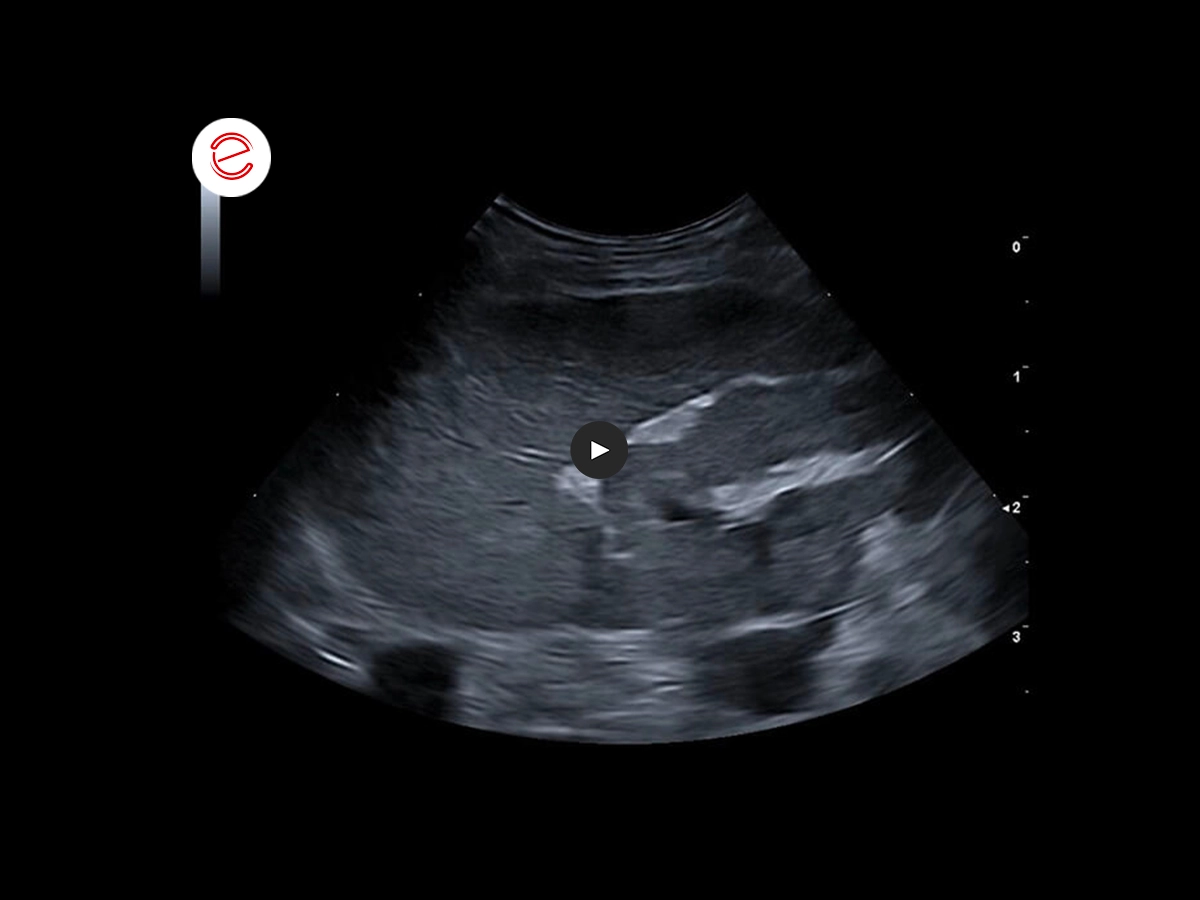

Ecografia dell'intestino

È stata eseguita un'ecografia addominale completa che mostra, tra gli altri risultati, un'anomalia dell'intestino tenue.

Nell'immagine ecografica si può apprezzare la stratigrafia dell'ansa digiunale, che presenta un'anomalia.

- All'esame ecografico, d'altra parte, nel soggetto si osserva uno strato soprannumerario. Le ipotesi avanzate a giustificazione degli strati digiunali soprannumerari, in ordine di possibilità, sono:

- infiltrazione/edema della mucosa

- infiltrazione/edema della sottomucosa

- banda iperecogena che divide le fasce dei muscoli longitudinali da quelle dei muscoli circolari.

Quando i sintomi si risolvono, il reperto scompare.